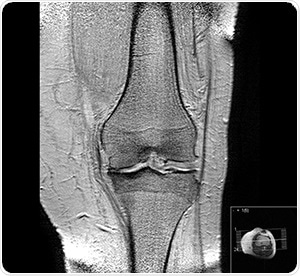

![Knee osteoarthritis stages II and III by Harrygouvas at Greek Wikipedia. [CC BY-SA 3.0 or GFDL 1.3], from Wikimedia Commons](https://www.appetitewellbeing.com/image-handler/picture/2018/12/1.jpg)

Knee osteoarthritis stages II and III by Harrygouvas at Greek Wikipedia. [CC BY-SA 3.0 or GFDL 1.3], from Wikimedia Commons

Osteoarthritis is a common degenerative condition. It is characterized by the diminution of cartilage in and around the joints which results in pain and loss of mobility. Age is seen to be the most common cause of osteoarthritis, but, traumatic joint injury can also cause joint degeneration in people of all ages. The progression of the condition can be slowed and symptoms can certainly be managed, however the underlying causes that lead to the development of this condition cannot be reversed.

Recent studies on osteoarthritis have led to the belief that changes to the subchondral (below the cartilage) bone structures, like thickening of the subchondral plate, are apparent prior to lesions or other symptoms becoming obvious in the cartilage itself.

The current standards giving recommendations on the diagnosis and treatment of osteoarthritis depend on radiographic imaging to detect either of two things. First, the hardening of the subchondral layer, or second, a reduction in joint space and visual and tactile inspection during arthroscopic surgery.